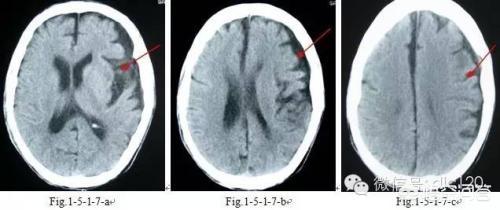

- しかし、臨床像の違いに加えて、時に臨床症状だけでは診断はできないまた、以下のような画像検査も行う。頭蓋CTと頭蓋MR.ラクナ梗塞にせよ脳梗塞にせよ、脳組織が虚血・低酸素状態にあるだけで、梗塞脳組織の液状化壊死はないため、24時間以内の頭部CTでは大きな変化はない。24時間以内であればある程度判別可能である。症状の急性期には、臨床では頭蓋MRが検査の第一選択となる。 MRIには様々なシーケンスがあり、症例によって異なるMRIシーケンスを用いて適切な検査を行うことができる。脳梗塞の診断において、DWIシーケンスは状況を明らかにするのに非常に直感的である。。

(3)検査:頭部のCT検査または核磁気検査。核磁気検査が最もよく、脳の対応する部分に空洞病巣を見つけることができる。

医学的定義では、ラクナ脳梗塞とは、大脳動脈から枝分かれした1本の細い血管の閉塞によって引き起こされる非皮質性の小さな梗塞である(梗塞病変の直径は通常0.2~15mm)。すなわち、ラクナ脳梗塞は、小さな動脈血管の閉塞によって引き起こされる脳の深部(非皮質)の小さな梗塞である。

脳梁性脳梗塞は無症状の人もおり、頭蓋骨のCTやMRI検査で発見されることが多い:

片麻痺、顔面神経麻痺、失語症、半盲症が60%、言語障害、嚥下障害、顔面神経麻痺、上肢の軽度の脱力が20%;

片麻痺が10%。

脳出血と脳梗塞は症状が同じであり、症状から判断することはできないので、脳梗塞とラクナ脳梗塞の診断は、脳CTや脳MRIでさらにはっきりさせる必要がある。